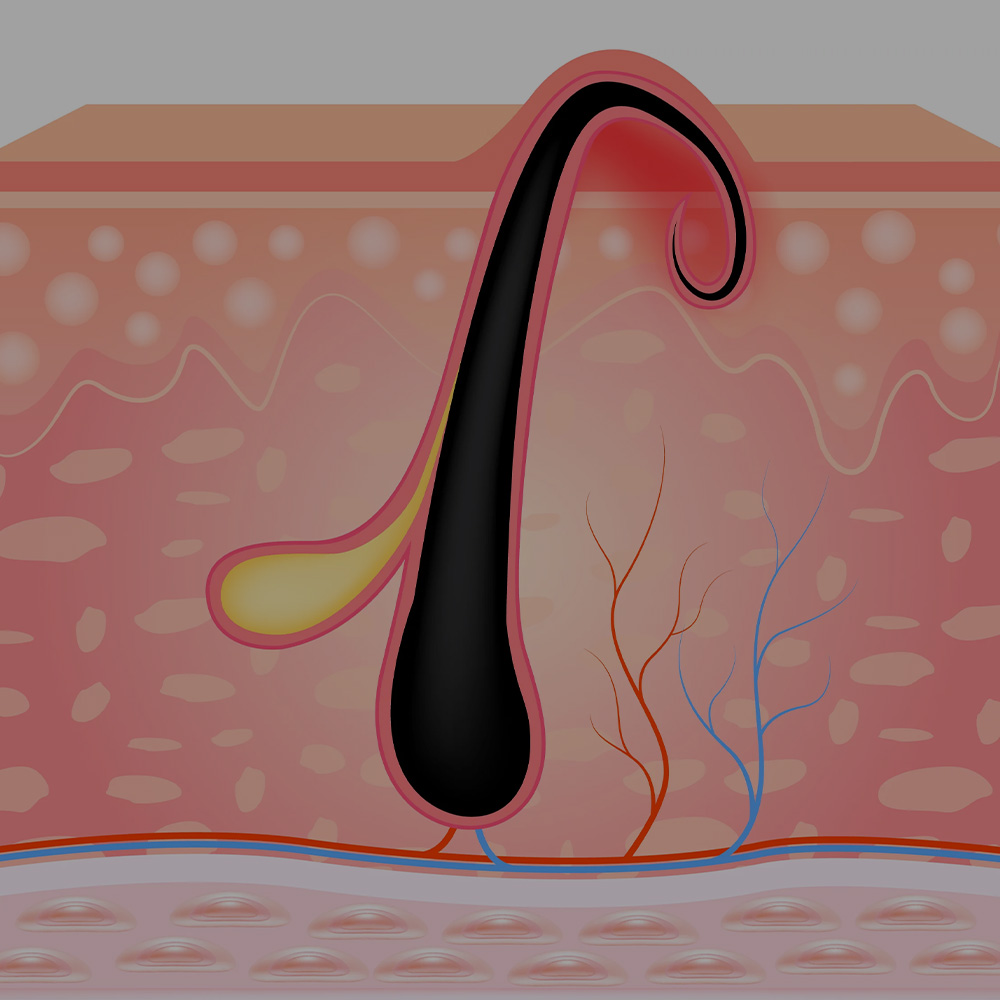

Kıl Dönmesi

Gelişmiş tıbbi çözümler sunarak sağlığınızı destekliyoruz. Kök hücre ve PRP tedavileri, obezite cerrahisi, metabolik cerrahi ve bireysel sağlık danışmanlığı hizmetlerimizle yanınızdayız.